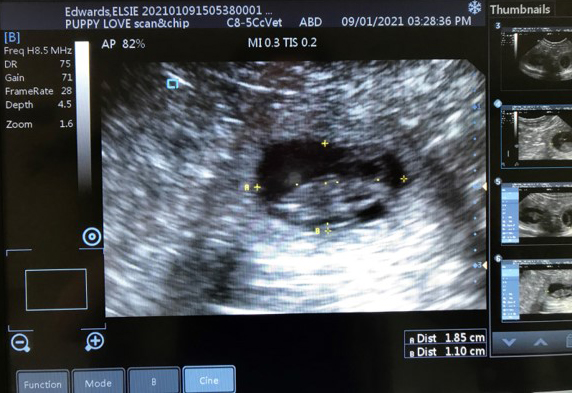

Ultrasound scans are a non-invasive, safe and painless procedure, used at various stages of pregnancy to gain greater insight and highlight potential problems that may occur.

To perform the scans I use a VIS Scan Pad + veterinary grade scanner (endorsed by the Animal Ultrasound Association) that offers superior image quality optimised for pregnancy detection & complies with international standards on ultrasonic safety.